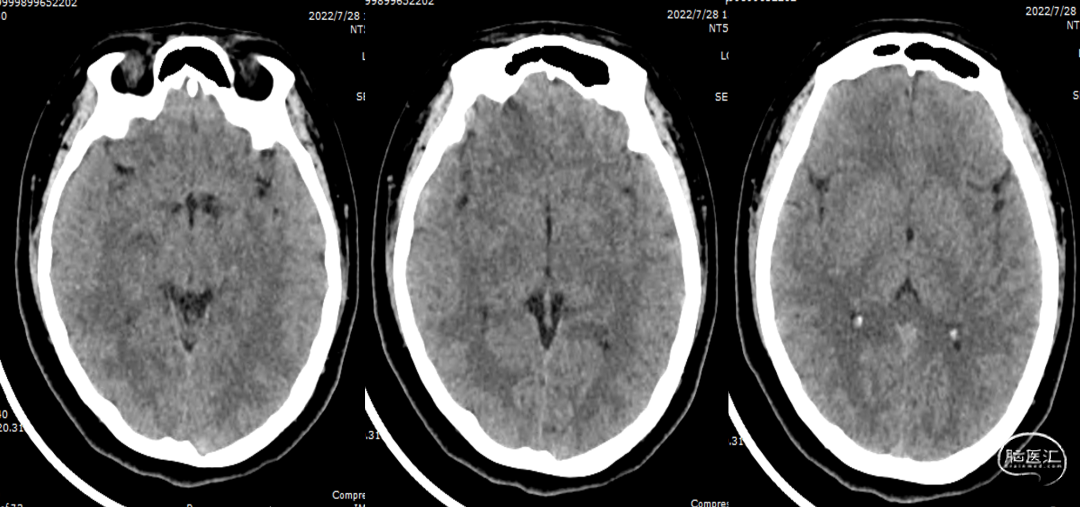

复查CT无梗死及出血征象。

术后第一次复查CT(2022-07-28)

半年后第二次复查CT(2023-01-17)